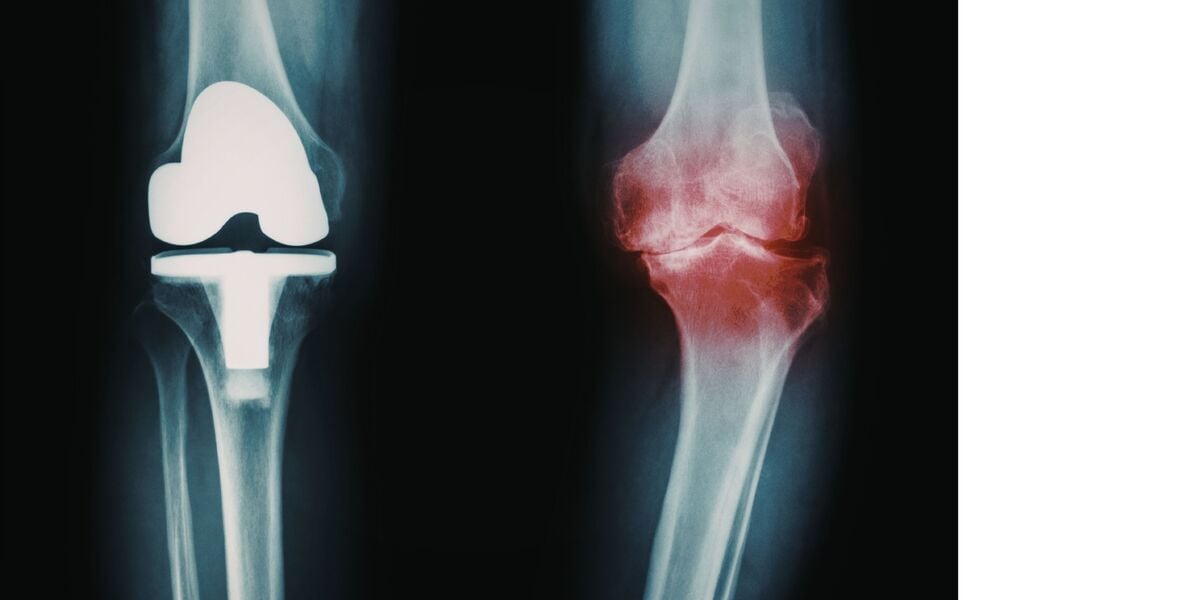

Every step, every movement, every grip—arthritis often turns these basic actions into challenges that many can’t imagine. With more than 180 million people in India alone affected by this condition, according to the Indian Council of Medical Research, the toll on joint health and daily comfort can be profound. Pain, swelling, and limited mobility become routine hurdles. How do your food choices factor into this daily battle?